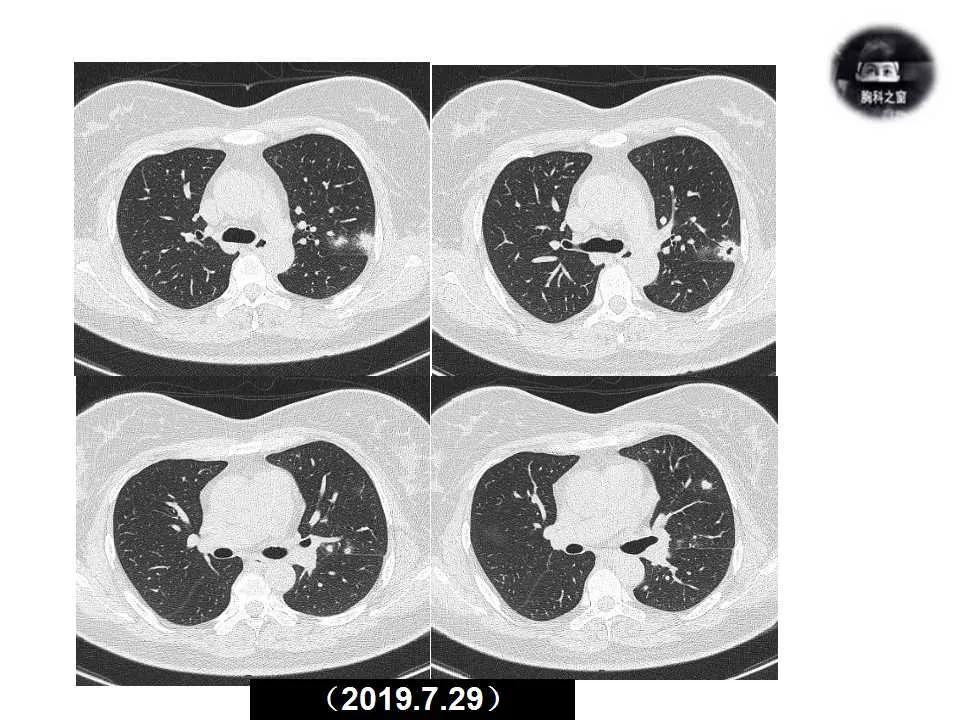

主诉:发现左肺病变1天

现病史:患者1天前体检胸部CT提示左肺病变,之前一段时间进食较少,七月初、七月中旬出现咳嗽、胸痛、无法深呼吸,无咯血,无乏力、盗汗,无明显体重减轻,为接受进一步诊治收入院。(2019.7.30)

影像诊断:真菌性肺炎,隐球菌可能性大。

追问病史,有近距离接触鸽子史。隐球菌抗原(+)。

肺隐球菌病